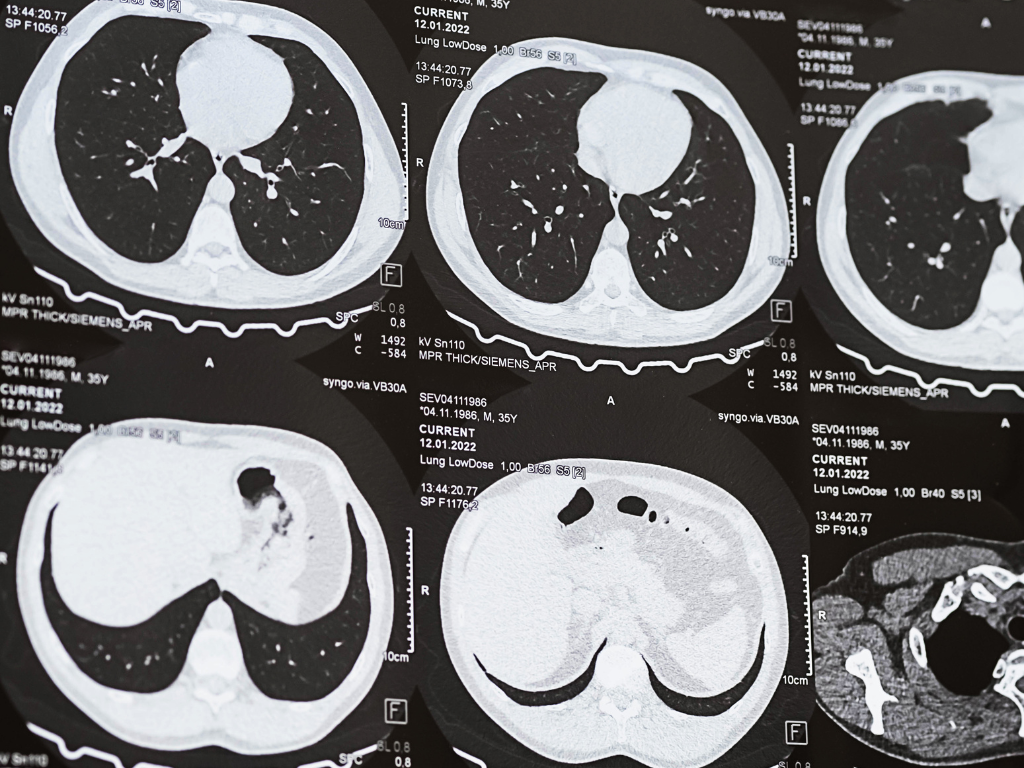

Grandes investigaciones internacionales —entre ellas, el ensayo clínico europeo NELSON— probaron que los programas de detección temprana con tomografía de baja dosis reducen la mortalidad por cáncer de pulmón en alrededor de un 20 %. Un logro notable para una enfermedad que históricamente se ha detectado en estadios avanzados, con las consabidas consecuencias en supervivencia. El estudio, en sí, es sumamente simple: ambulatorio, no invasivo, dura unos diez minutos y no requiere preparación previa. La diferencia con una tomografía convencional está en la dosis de radiación, significativamente menor; equivalente, dicho sea de paso a la de unas 15 radiografías de tórax.

“Una tomografía estándar es como una cámara profesional con un flash muy potente: permite ver todo con muchísimo detalle. La tomografía de baja dosis, en cambio, es como sacar una foto con muy buena luz natural: la imagen sigue siendo nítida, pero con mucha menos exposición”, explica el especialista. En el pulmón, esa reducción no compromete la calidad diagnóstica: el tejido se visualiza muy bien incluso con dosis bajas.

Gracias a esa resolución, el estudio detecta nódulos cuando todavía se cuentan en milímetros. Para dimensionar la diferencia: una radiografía recién identifica lesiones cuando ya miden alrededor de 2 centímetros. Con la tomografía de tórax de baja dosis, hablamos de tumores de 3 a 4 milímetros.

En efecto, el screening no consiste en hacer una tomografía suelta. Forma parte de un programa estructurado, con criterios estandarizados de lectura e interpretación. Las imágenes se informan según el sistema Lung-RADS, que clasifica los nódulos de acuerdo con su probabilidad de malignidad y orienta la conducta a seguir: desde continuar con controles habituales hasta adelantar estudios o derivar a evaluación especializada.